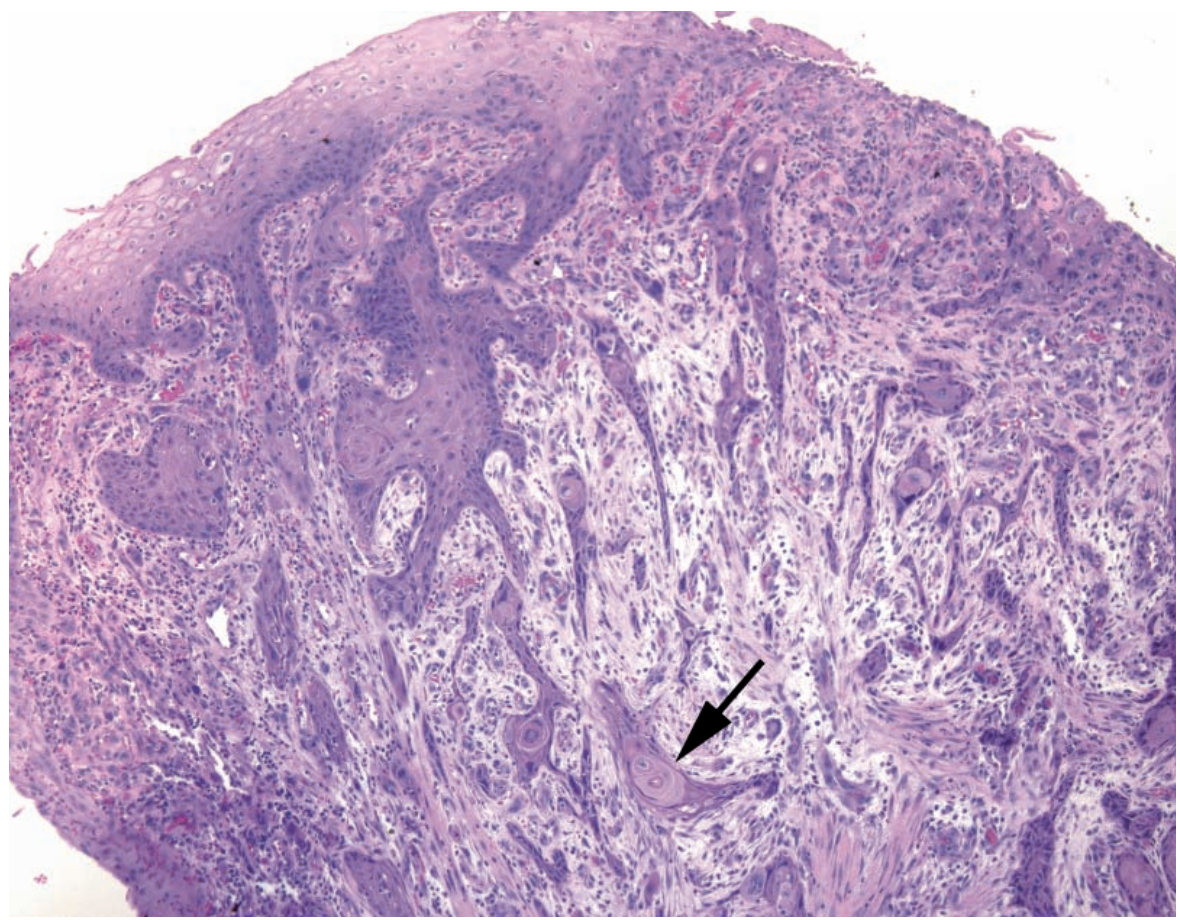

A

Invasive squamous cell carcinoma

Arrow: Deep aberrant keratinization